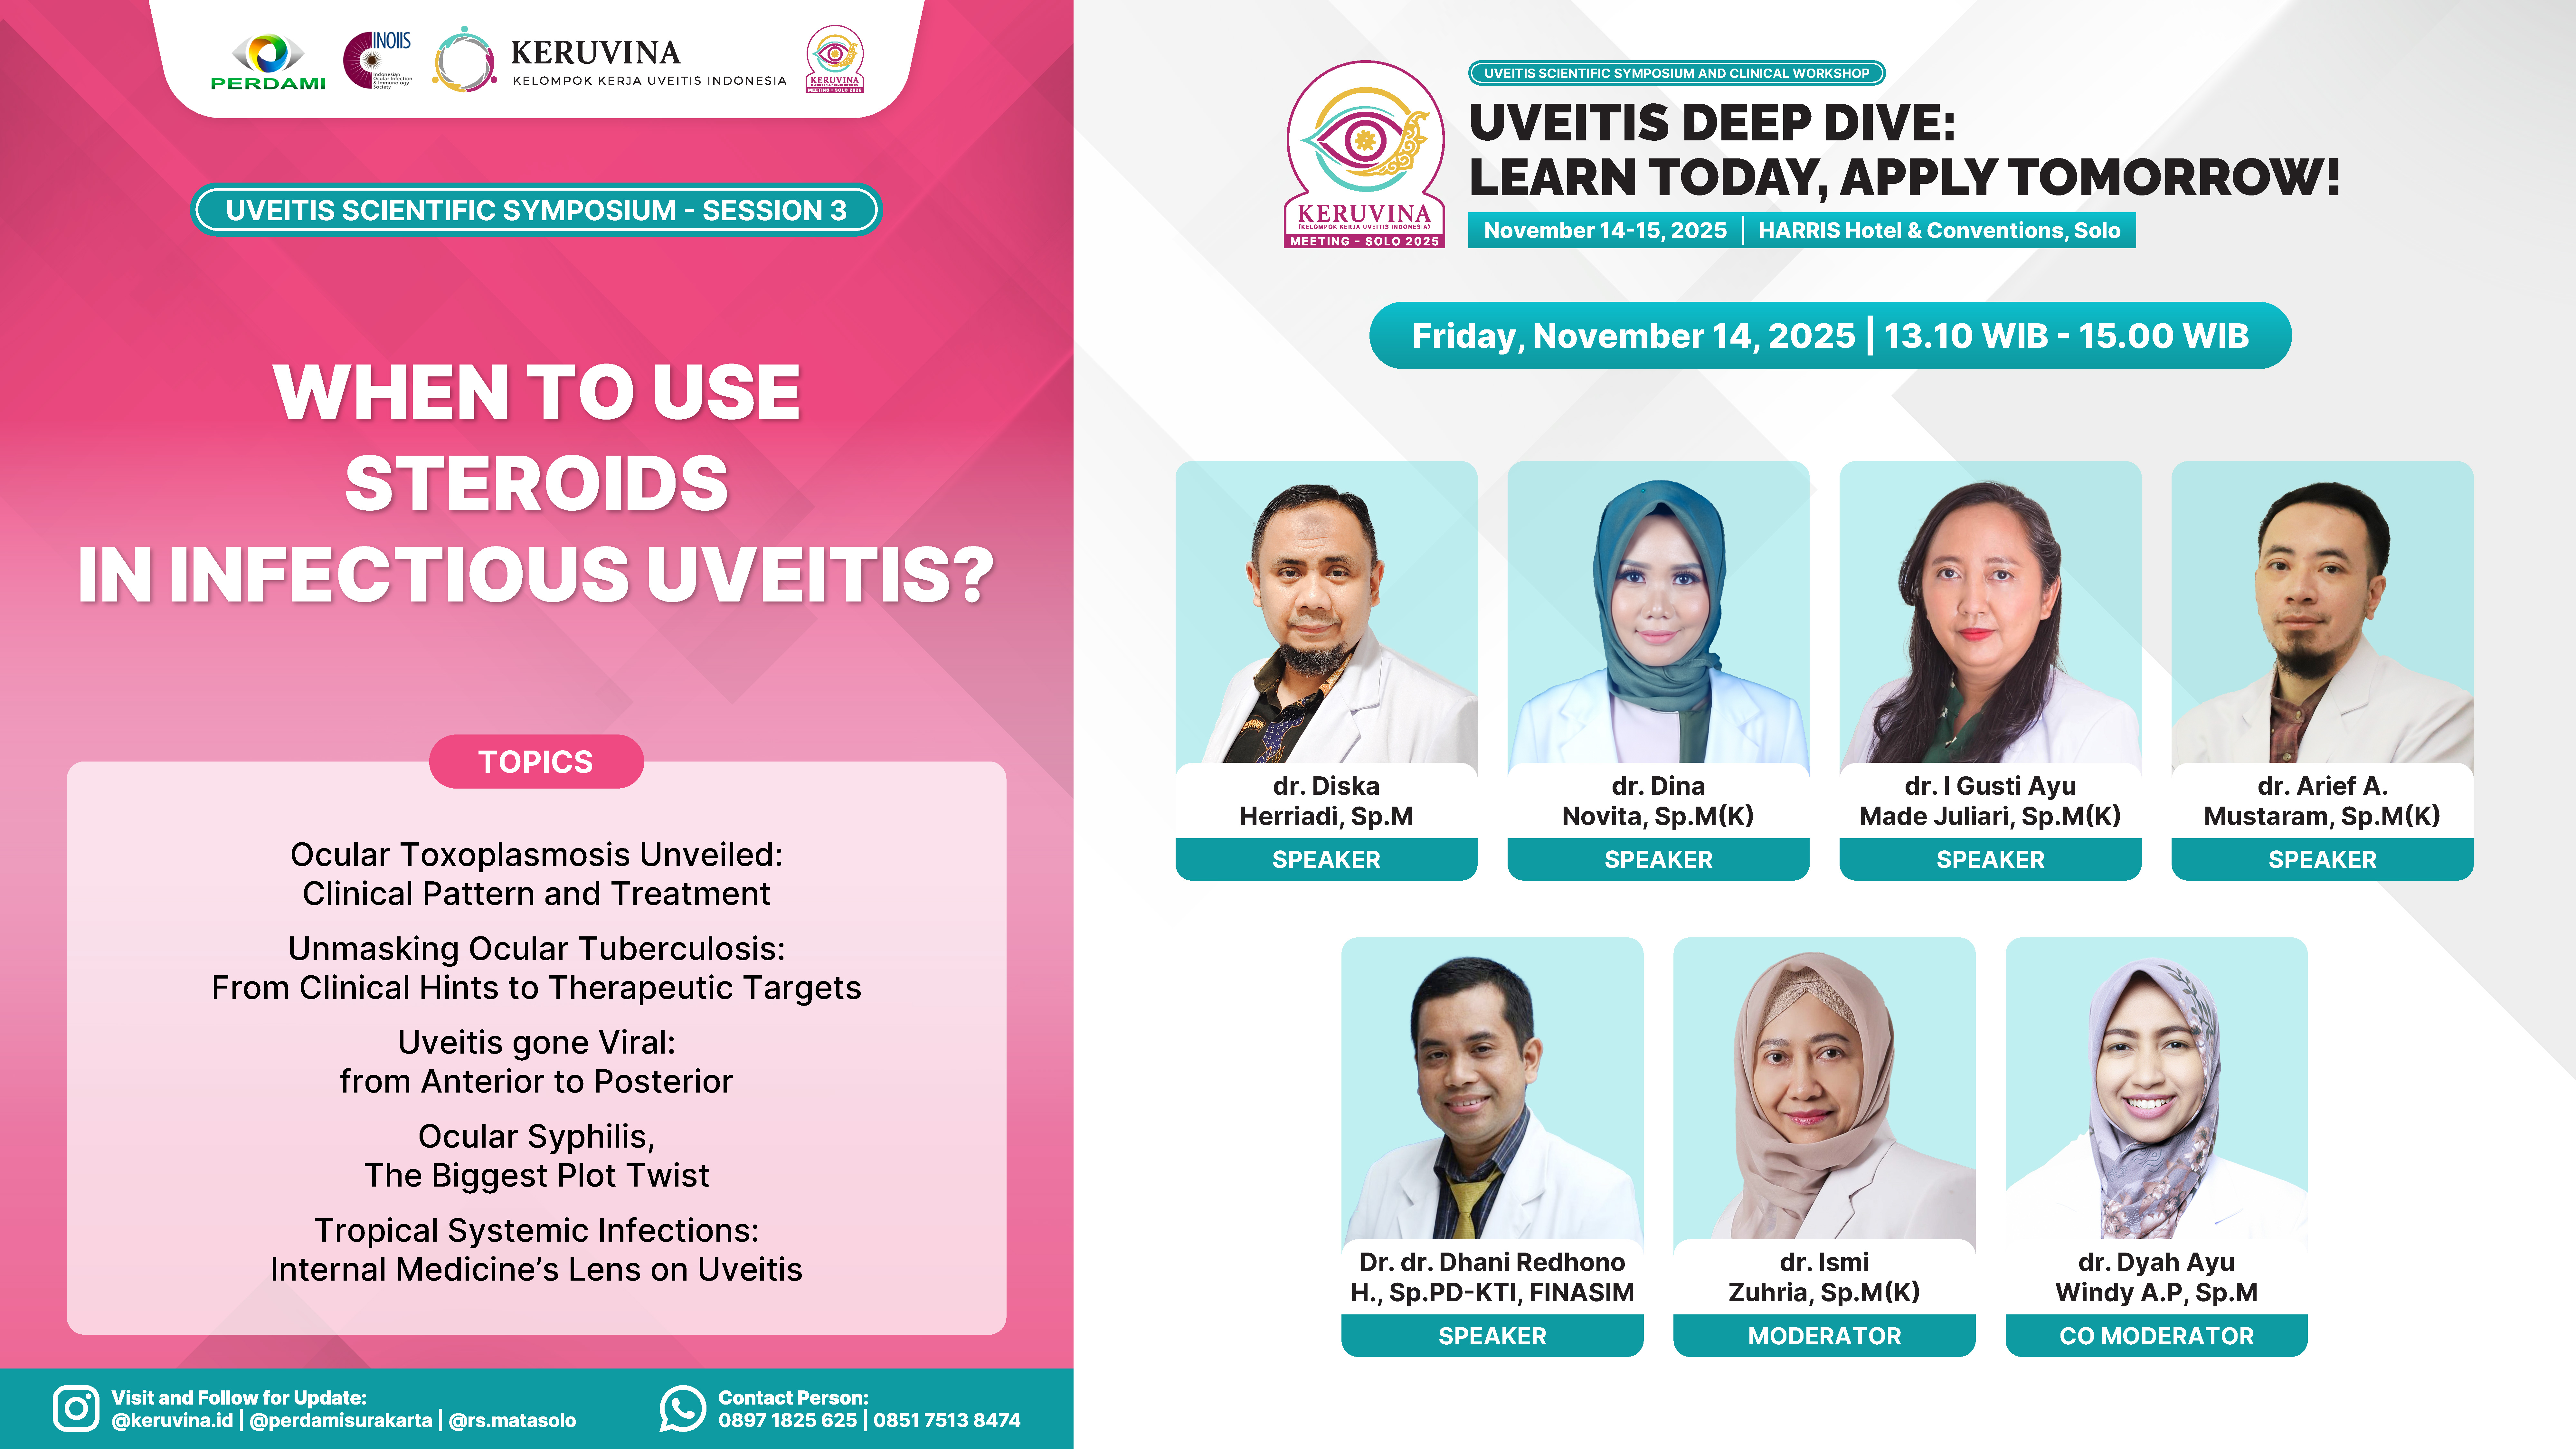

Enhance your skills with interactive case-based sessions and multimodal imaging workshops.